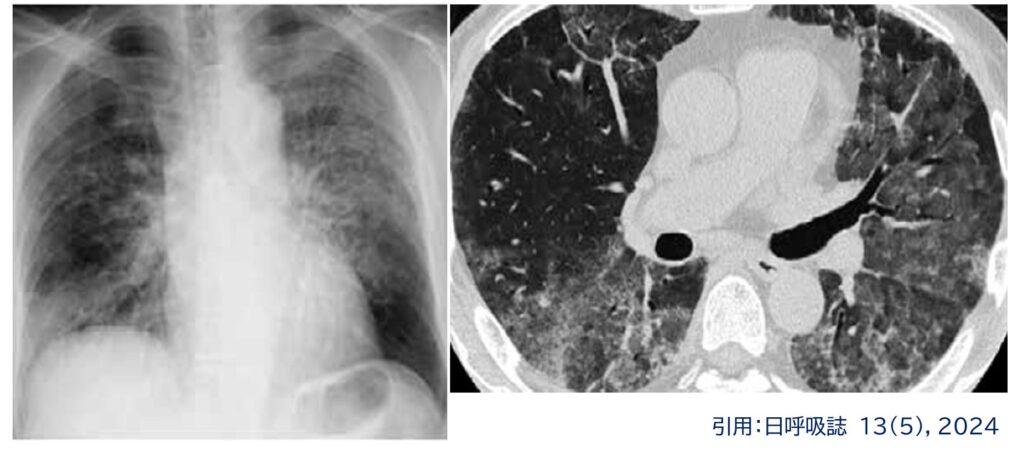

画像・病理学的に、

多様なパターンを示し、NSIPパターン、OPパターン、HPパターン、DADパターンなどがあります。

このうちDADパターンは、肺水腫様の所見を呈することがあり、今回の症例はこの画像パターンに相当します。

さらに、スライドに示すように、

ARDS、すなわち肺水腫様のDADパターンを呈する場合には、感染症、心不全、敗血症などとの鑑別が必要です。しかし原因がはっきりしない場合には、薬剤性も必ず鑑別に挙げる必要があります。